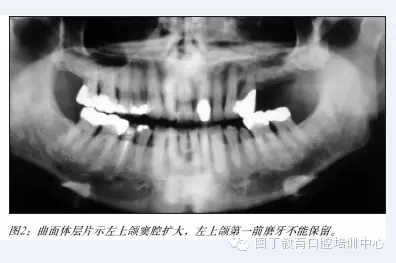

據(jù)筆者可獲得的有限的研究表明:術(shù)者經(jīng)過專業(yè)培訓(xùn),選擇適當(dāng)?shù)牟±项M竇提升植骨術(shù)是一項(xiàng)成熟的種植外科技術(shù)(見圖2-6),種植體植入移植骨后的五年成功率達(dá)到95%以上。